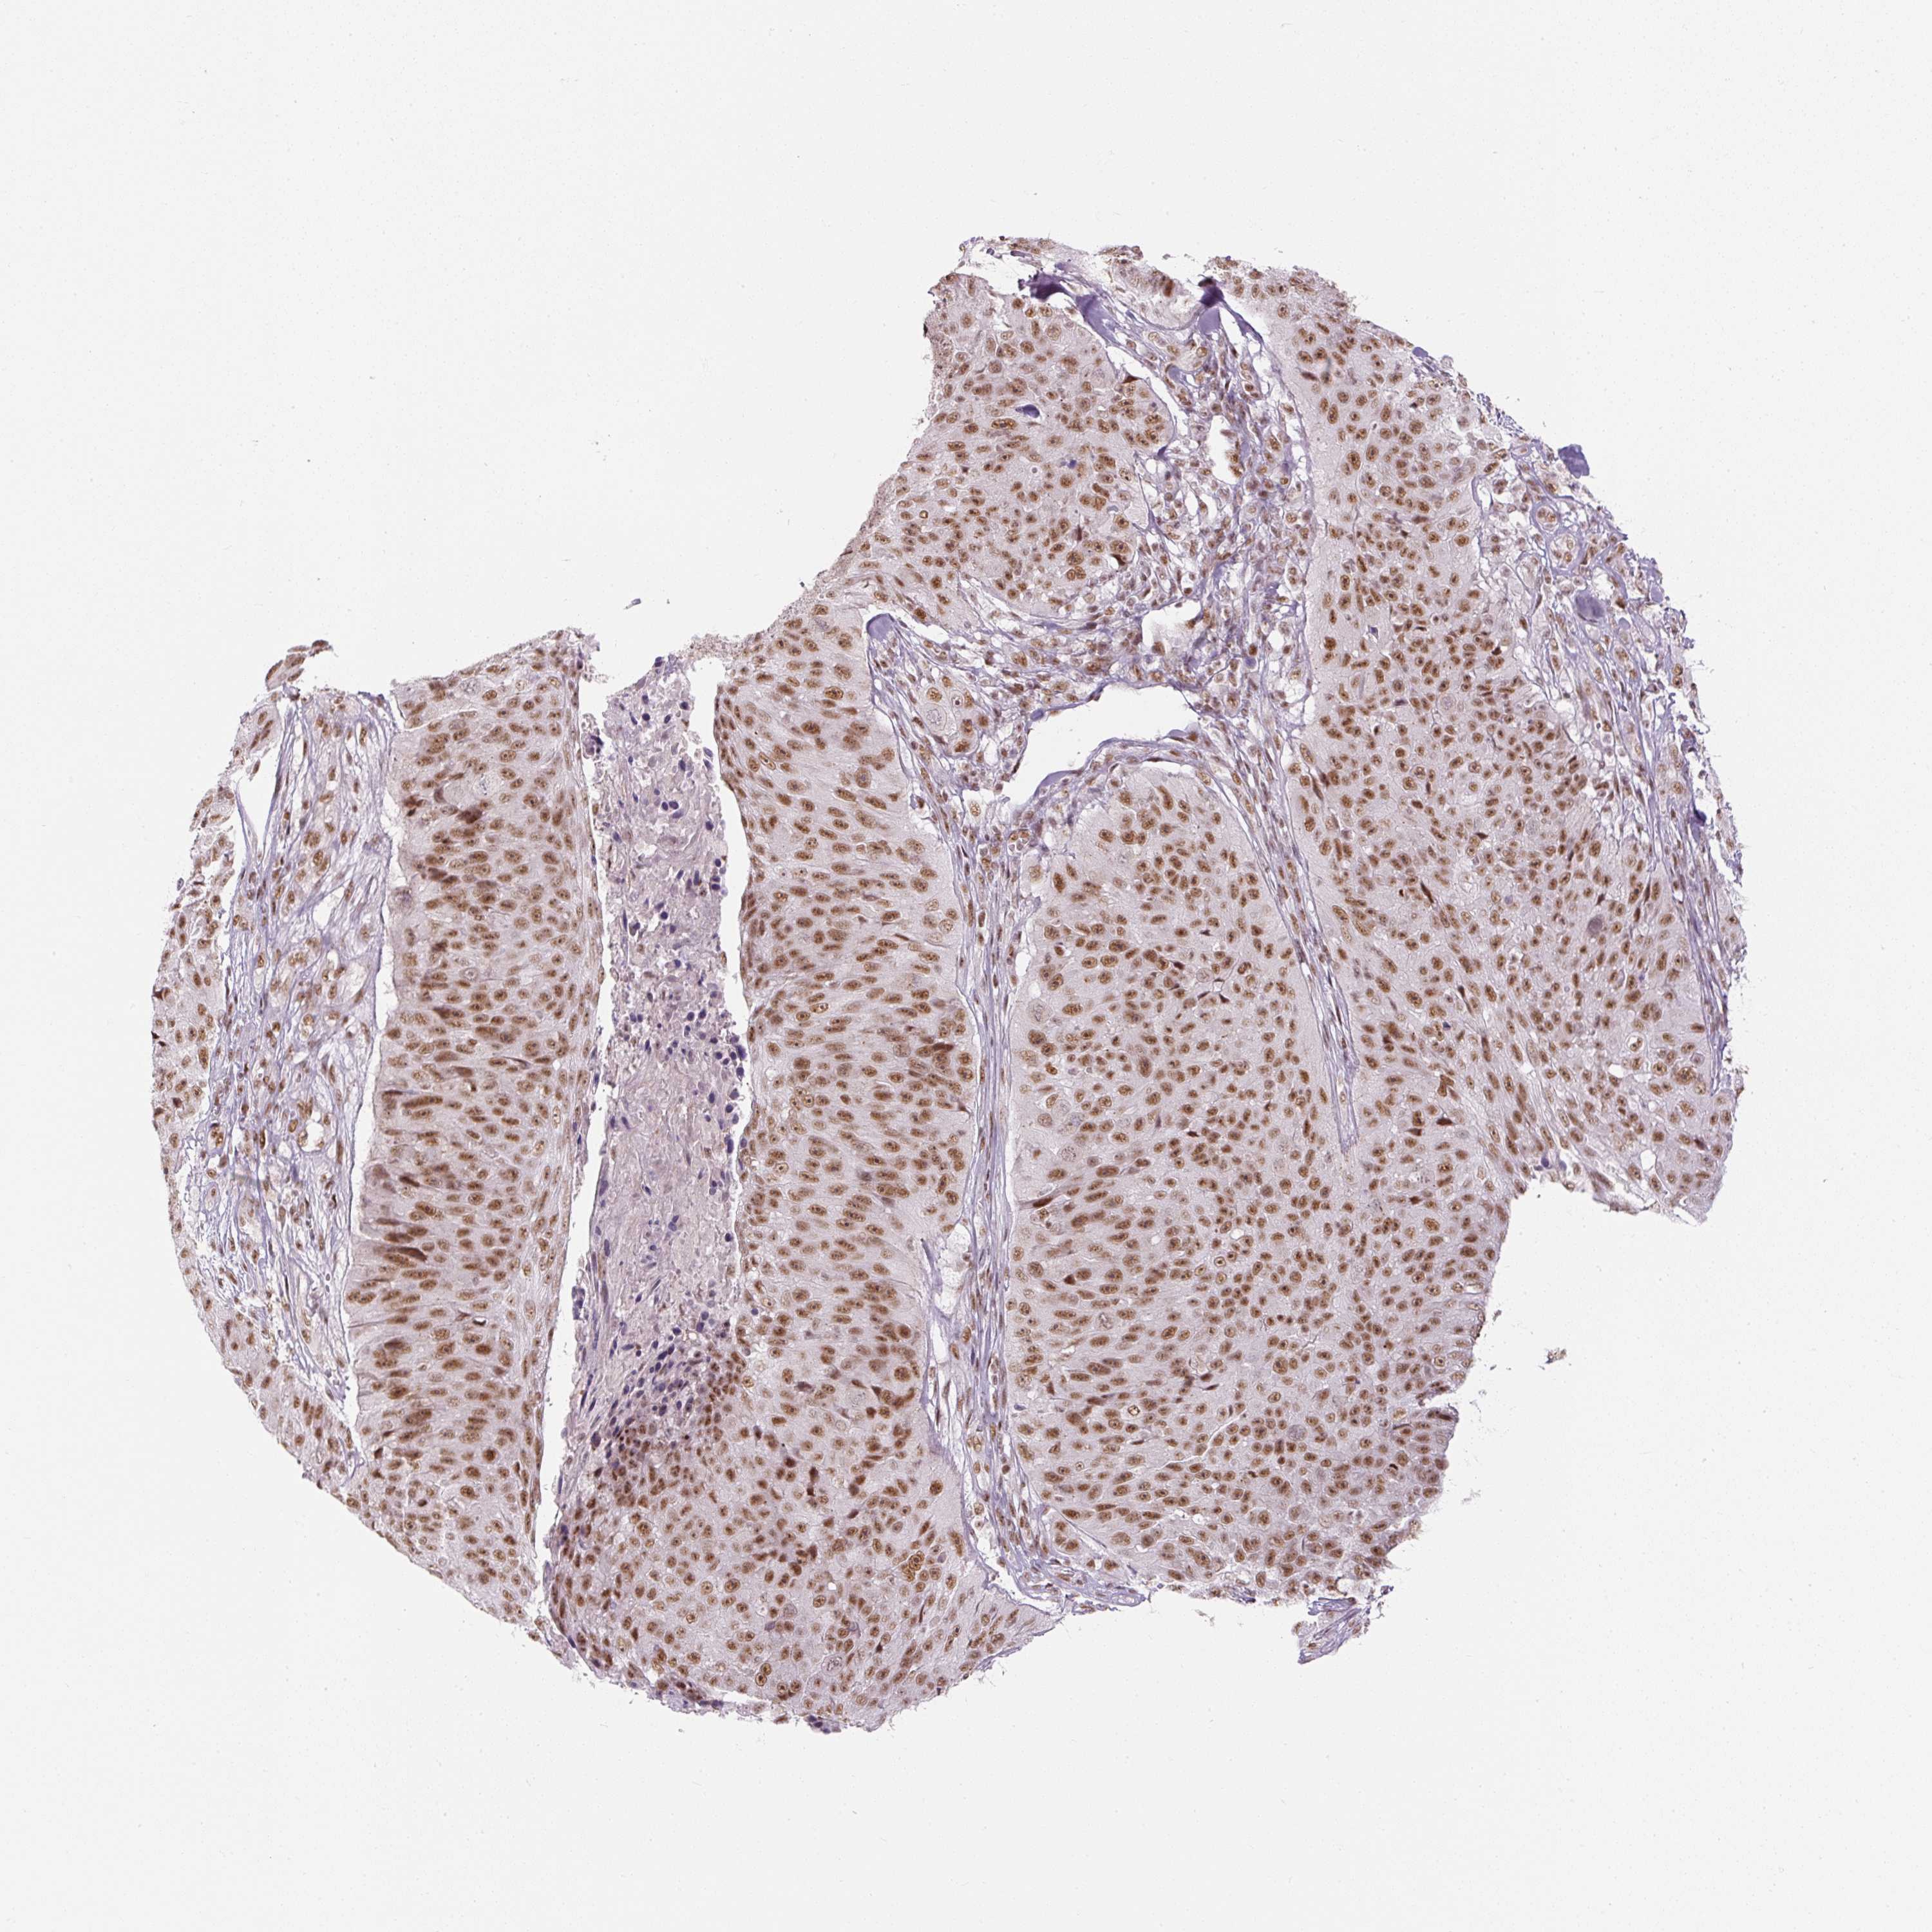

SKIN CANCER - Protein expressioni

A mouse-over function shows sample information and annotation data. Click on an image to view it in a full screen mode. Samples can be filtered based on level of antibody staining by selecting one or several of the following categories: high, medium, low and not detected. The assay and annotation is described here.

Antibody stainingi

Antibody staining in the annotated cell types in the current human tissue is reported as not detected, low, medium, or high, based on conventional immunohistochemistry profiling in selected tissues. This score is based on the combination of the staining intensity and fraction of stained cells.

Each image is clickable and will lead to virtual microscopy that enables deeper exploration of all samples and also displays staining intensity scores, fraction scores and subcellular localization as well as patient and tissue information for each sample.

Antibody HPA043562

Antibody CAB010910

Basal cell carcinoma

Squamous cell carcinoma, NOS

Squamous cell carcinoma, metastatic, NOS

Papilloma, NOS